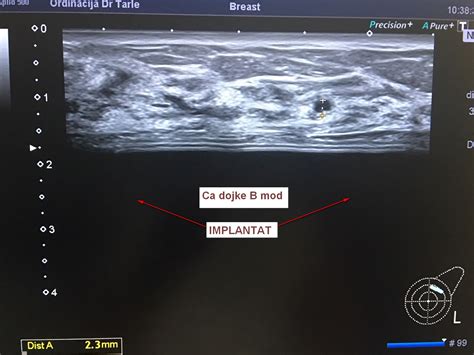

Ultrazvok: To je pogosto prvi slikovni test, ki se uporablja za oceno bulice v dojki. Ultrazvok je zlati standard pri diagnosticiranju cist. S pomočjo visokofrekvenčnih zvočnih valov zdravnik dobi natančno sliko notranjosti dojke. Na ultrazvočni sliki se ciste pokažejo kot gladko omejene, okrogle ali ovalne strukture, napolnjene s tekočino, ki je črne barve. Zdravnik lahko natančno izmeri njihovo velikost, oceni njihovo obliko in preveri, ali imajo tanko steno. Če slika ustreza vsem kriterijem za preprosto cisto, nadaljnje preiskave pogosto niso potrebne.